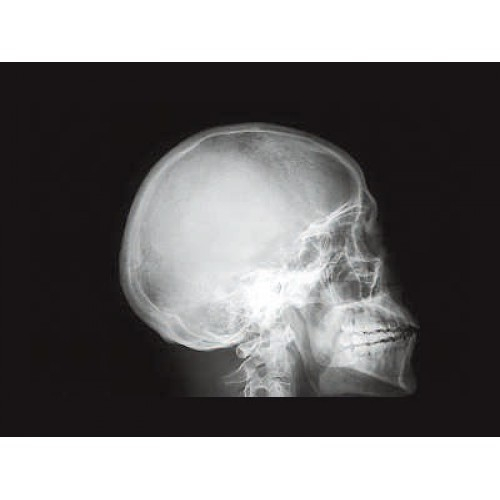

Профессиональный стационарный рентген GE XR 6000 представляет собой современное диагностическое оборудование премиум-класса. Аппарат разработан для проведения широкого спектра рентгенологических исследований с высочайшей точностью и детализацией изображений.

- Обзорной и прицельной рентгенографии всех анатомических областей

- Исследований опорно-двигательного аппарата